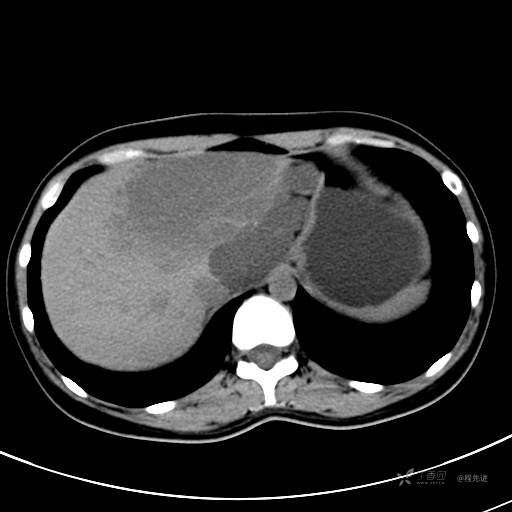

CT平扫+增强,每个序列3张图

CT值 平扫48HU 动脉期66HU 静脉期68HU 延迟期62HU